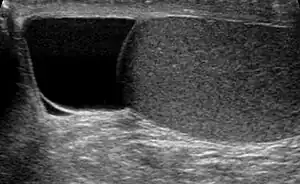

| Ultrasound of a testicle (grey) and a spermatocele (black). | |

The primary care physician may diagnose and manage benign causes of scrotal masses such as hydrocele, varicocele and spermatocele. However, if a "must not miss" diagnoses related to testicular masses such as testicular torsion, epididymitis, acute orchitis, strangulated hernia and testicular cancer is suspected, the family physician must refer to a urologist.[16] Finding a painless, cystic mass at the head of the epididymis that is clearly separate from the testicle can indicate a spermatocele. Shining a light through the mass through a process known as transillumination can also help differentiate between a fluid-filled cyst and a tumor, which would not allow as much light to pass.[17] If uncertainty exists, ultrasonography of the scrotum can confirm the presence of a spermatocele.[14] The location and history of any scrotal masses are crucial in determining whether or not the mass is benign or malignant.[18] Lab tests such as a complete blood count (CBC test) or urine test can also be conducted to check for any possible infection or signs of inflammation.[19]

Spermatoceles come in varying sizes and shapes. Some spermatoceles are very small and can only be detected through an ultrasound. More commonly seen are spermatoceles that are a pea-sized lump. They tend to form above or behind a testicle and have a shape and size that looks like a pea. Larger growths have been reported to look similar to a third testicle and can be very discomforting.[19] For those who are affected with large spermatoceles, some have reported feeling pain, heaviness, and fullness in the affected testicle.[17]

Upon physical examination, if a 'lump' is found during the testicular exam, further screening may be performed via ultrasound to eliminate testicular cancer.[8]

Spermatoceles usually affect men who are middle-aged and can, although rarely, affect children during puberty.[23] The incidence rate is around 5-20% for children.[24] It is estimated that approximately 30 percent of men have been diagnosed with small spermatoceles while less have larger spermatoceles. The incidence of spermatoceles increases as men age.[25] Before puberty, children from the male sex may develop a similar benign mass called epididymis cyst. Although both epididymis cyst and spermatocele may be referred as the same, the epididymis cyst does not contain sperm and it can occur anywhere within the epididymis. It can be differentiated through an ultrasound imagining. Epididymis cysts larger than 10mm in diameter are recommended for surgery but if there is no problem then surgery is discouraged as it can affect fertility in the future.[11]